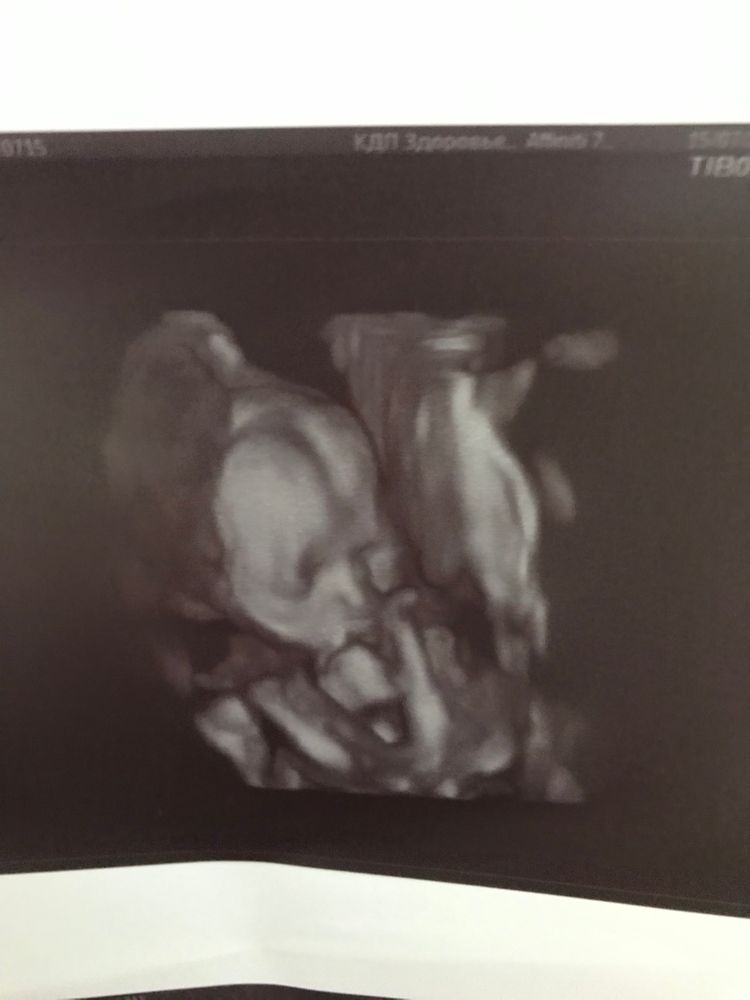

2 скрининг, завтра уже 20 недель🥳

Всё о нашей беременностиМалышка развивается в соотвествии со сроком, все в норме💓💓💓

очень переживала за количество вод, живот не большой, боялась, вдруг ей там тесно. Но тоже все в норме и рыбке нашей там хорошо🥰 Крошечка совсем 311г